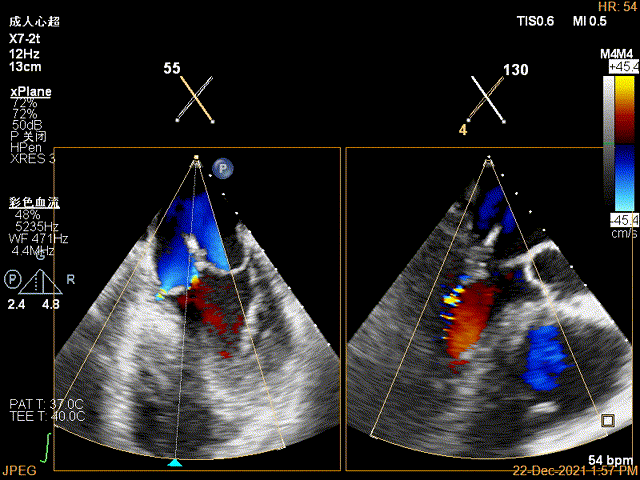

Bicom:MR(重度),反流束宽22mm,反流面积24.2cm²,PISA法定量EROA:2.3cm²,Rvol:274ml,RF:57%,r:16mm。

3D-color MV view:大量反流,起源于2区

TEE Bicom view:二尖瓣后叶P2区大范围脱垂,部分累及1区及3区

Color-view:极大量反流,主要来源于2区